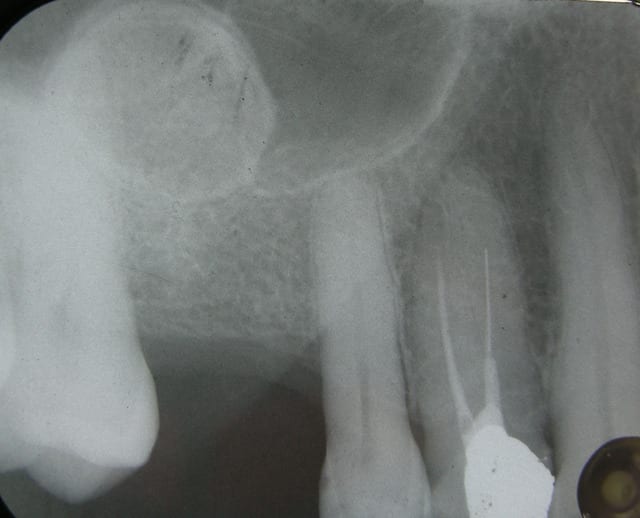

bonjour à tous, petite image en couché de soleil, dans un sinus, d'aspect osseux.

déjà présente sur une radio de mon prédécesseur en 2005.

de quoi s'agit il?

très beau résultat de sinus lift réalisé par la méthode du ballonnet!

bon, ok! plus sérieusement, je ne vois pas ce que ça peut être mais comme tu dis, ça a la densité de l'os.

il faudrait avoir l'historique de la dent extraite (je pense à un kyste péri-apical qui se serait ossifié ou un petit dépassement de produit d'obturation qui aurait entraîné une calcification etc..)

Le plus étrange c'est que ça apparait comme différencié ou encapsulé, avec une zone plus dense sur toute la périphérie. Il serait intéressant d'avoir un cône beam.

ça peut être un ostéome intra-sinusien tout simplement.

les sinus de la face sont une topographie assez commune pour ce type de lésion mais surtout au niveau fronto-ethmoïdal.

c'est vrai qu'au niveau maxillaire c'est assez rare.

si il y a ostéomes mutiples aussi bien cranio-faciaux que au niveau des membres, il est légitime de suspecter un syndrome de gardner dont le risque majeur est un cancer colo-rectal à terme.

tu mesures la densité du tissu à partir d'un scan, avec un cone-beam ça me semble pas possible d'avoir l'information exacte de denisté en unité Hounsfield

tu utilises alors l'ostéome comme site d'implantation, ça te fait un petit "case report" original.